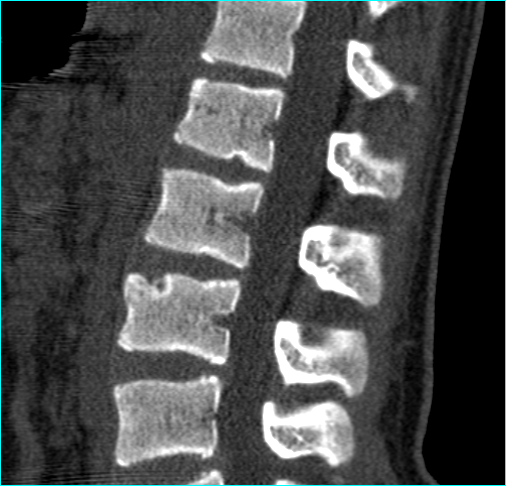

schmorl结节伴骨髓水肿(典型mri)

schmorl结节伴骨髓水肿(典型mri)_病变_纤维_造影